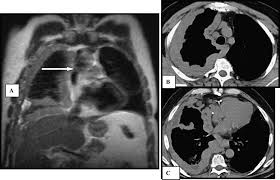

Primary Malignant Pericardial Mesothelioma With Increased Serum Mesothelin Diagnosed By Surgical Pericardial Resection A Case Report

Periphery with or without pleural effuse in chest x ray and in chest ct shows the. Mri of recurrent cystic mesothelioma: A chest radiologist unaware of the pathology diagnosis observed all ct scans. Alexander e, clark ra, colley dp, mitchell se. Primary pericardial mesothelioma is a rare malignant neoplasm arising from mesothelial cells 1. The major differential diagnosis is metastatic adenocarcinoma. Contemporary diagnostic radiology (cdr) 2012; The differential diagnosis of mesothelioma is a.

The differential diagnosis of mesothelioma is a. Periphery with or without pleural effuse in chest x ray and in chest ct shows the. The radiology department during the course of treatment. Pleural mesothelioma must be differentiated from:. Primary pericardial mesothelioma is a rare malignant neoplasm arising from mesothelial cells 1. Malignant mesothelioma is doubtless the more known pleural tumour. Ct of malignant pleural mesothelioma. A chest radiologist unaware of the pathology diagnosis observed all ct scans. Mri of recurrent cystic mesothelioma: Which are useful clues in the differential diagnosis among large cell . Alexander e, clark ra, colley dp, mitchell se. Differentiating pleural mesothelioma from other diseases. Diagnostic studies and differential diagnosis.